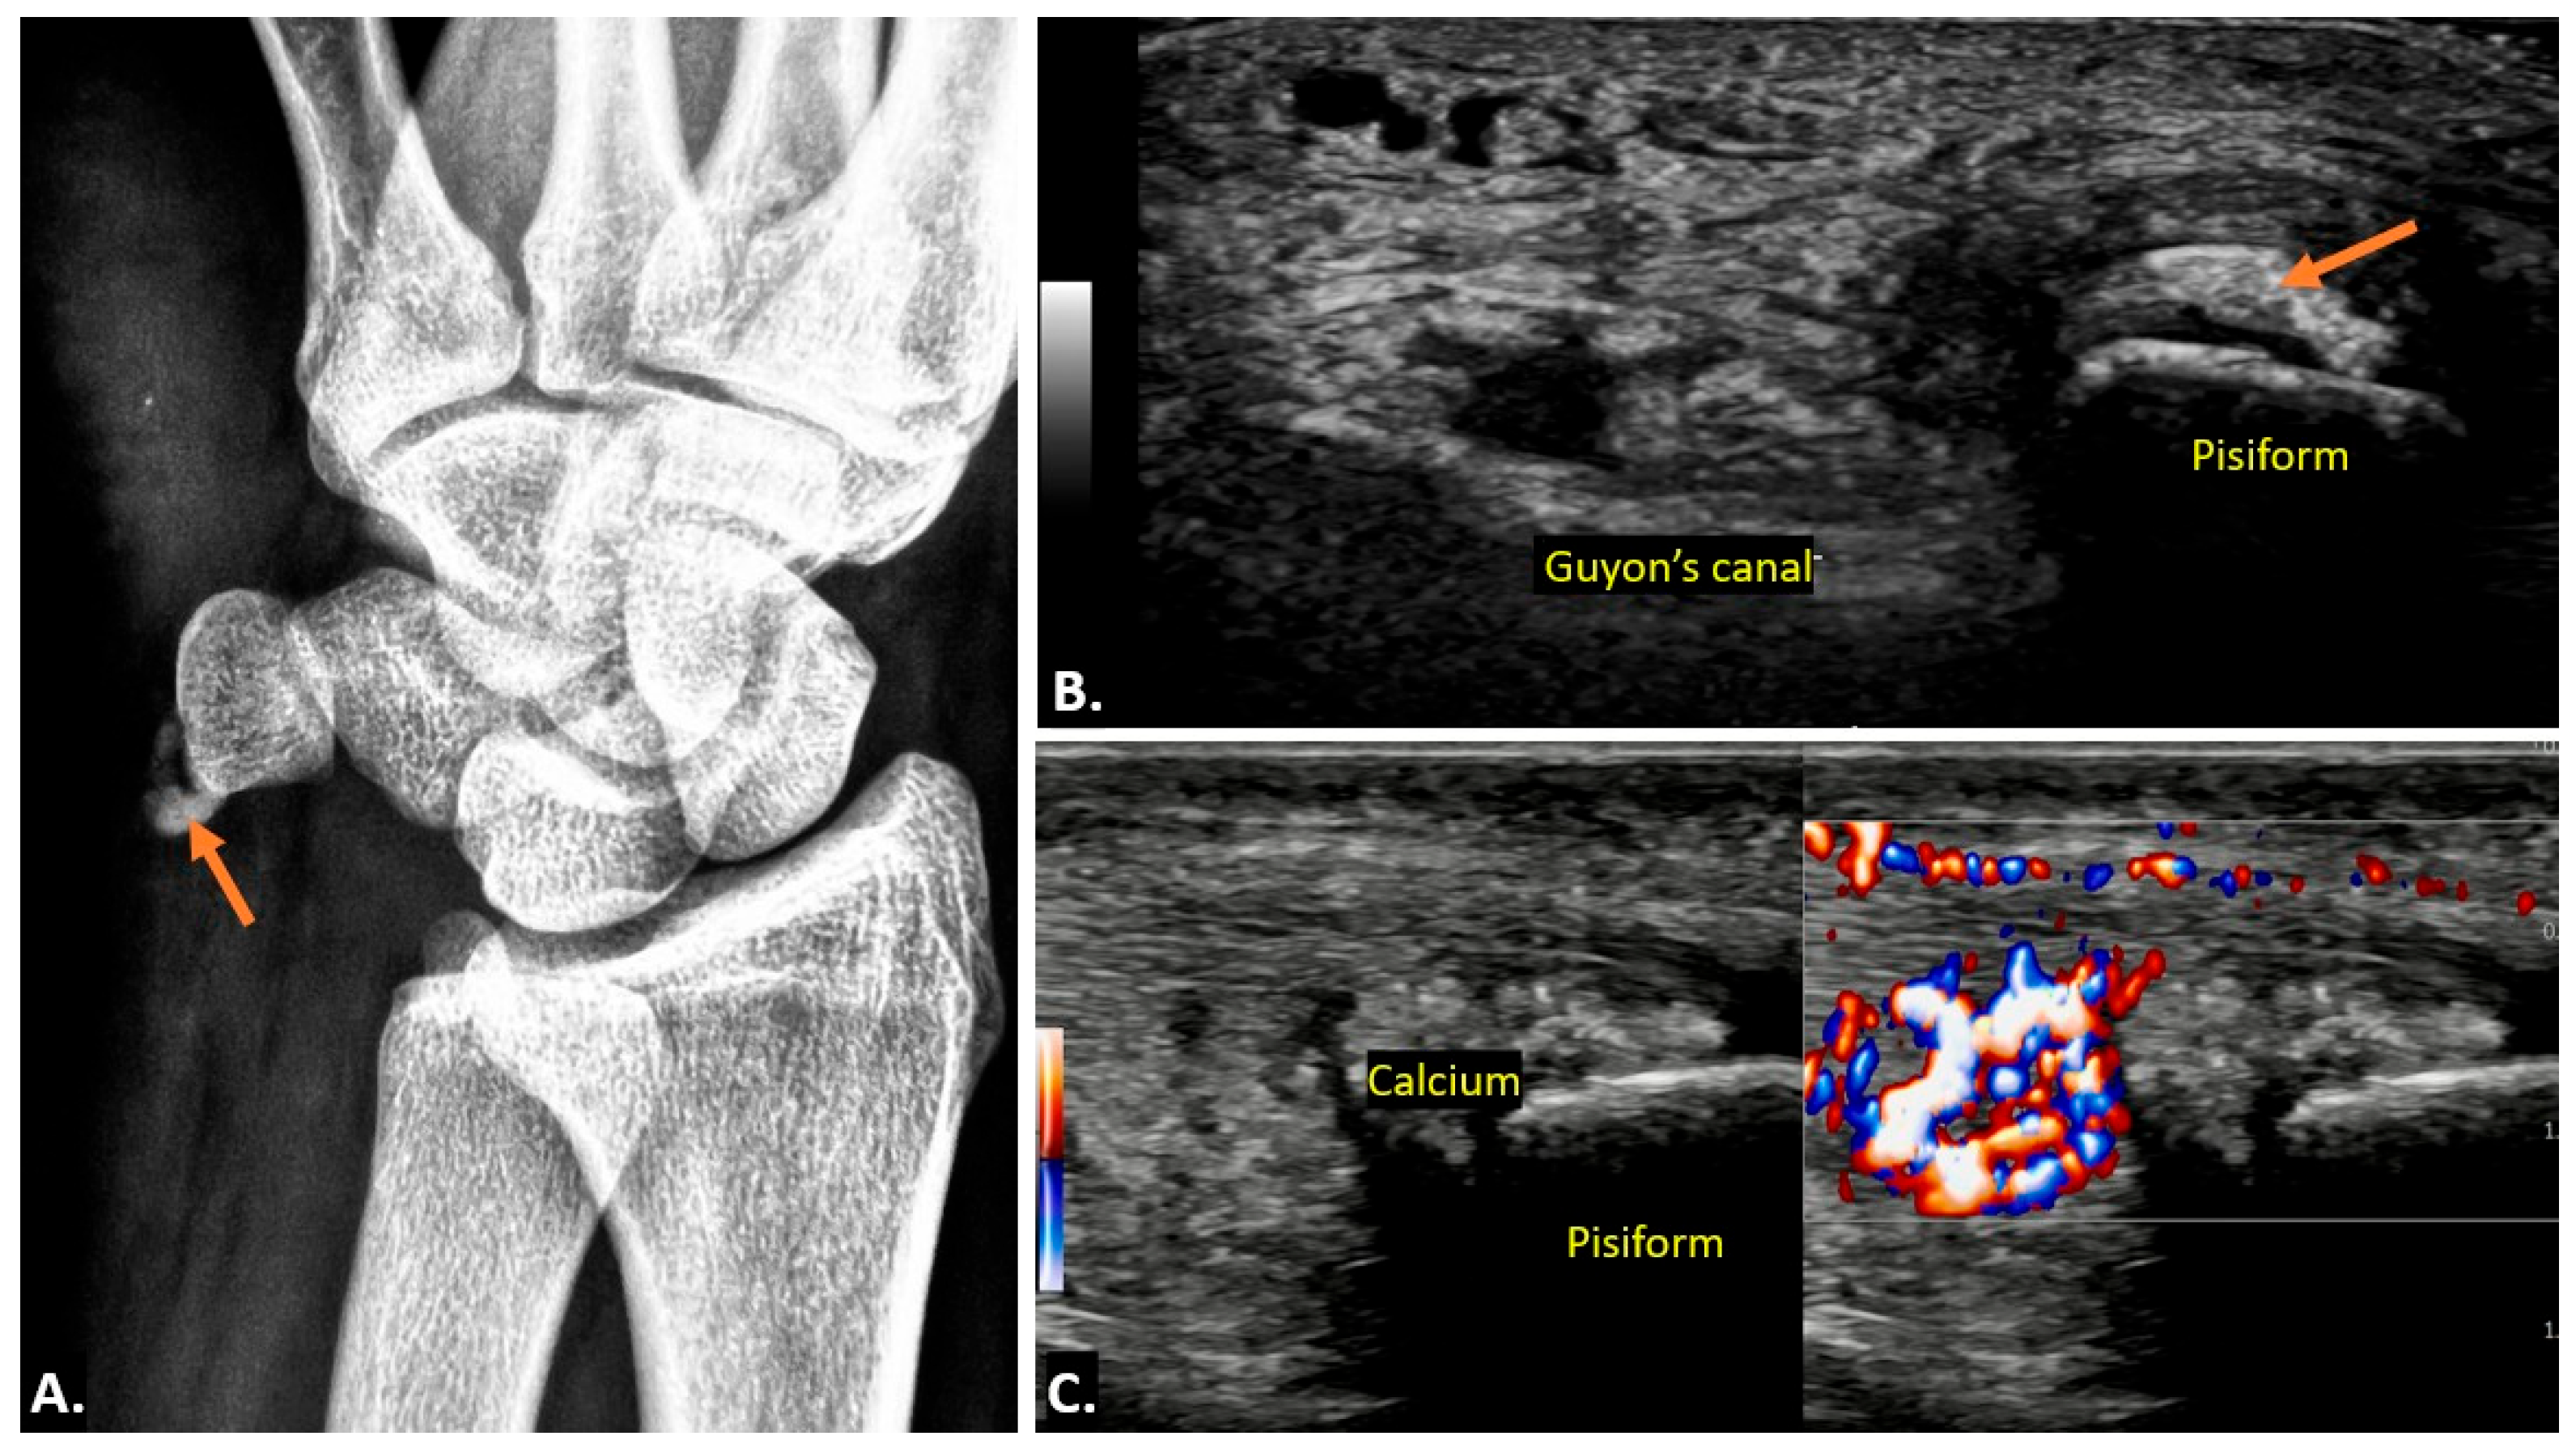

4.5. Flexor Carpi Ulnaris Calcific Tendinopathy

| Flexor Carpi Ulnaris Calcific Tendinopathy | Hyperechoic foci with posterior acoustic shadowing. Chronic cases: well-delineated deposits. Acute cases: surrounding soft-tissue oedema and increased vascularity on Doppler. | Low signal calcifications on T1/T2. High signal in inflamed soft tissues on T2. Soft-tissue enhancement in acute cases. |